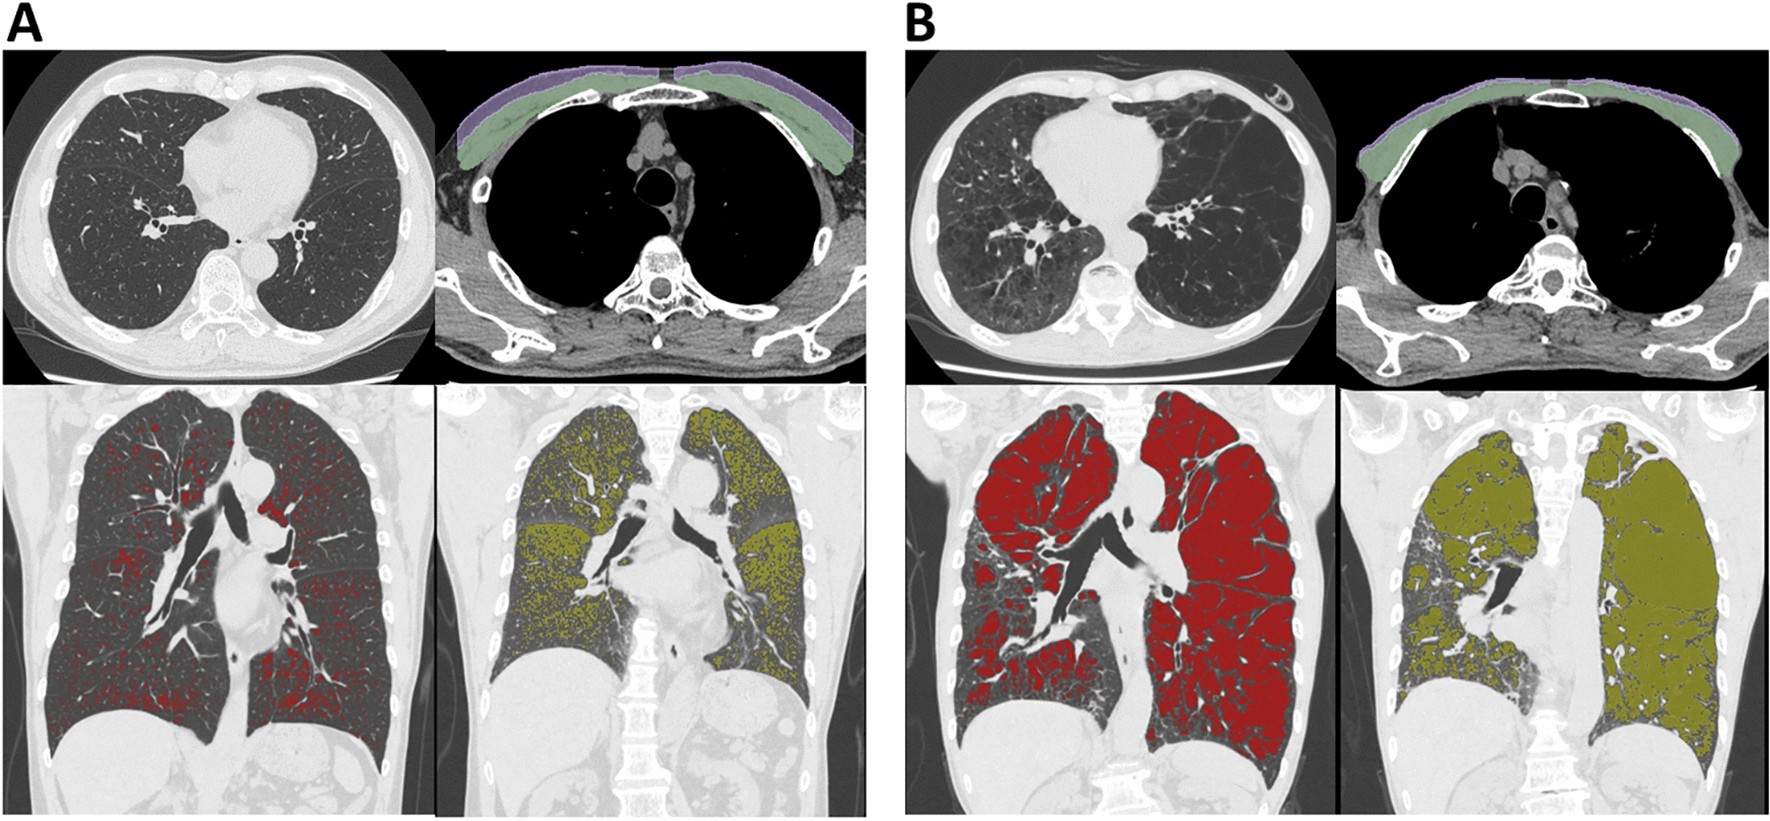

Figure 3

Examples of pulmonary and extrapulmonary CT findings in symptomatic patients with and without physical inactivity. (A) Inspiratory and expiratory CT in symptomatic patient with COPD and preserved physical activity (COPD assessment test [CAT] = 20 and Life-Space assessment [LSA] = 96). (B) CT in symptomatic patient with COPD and impaired physical activity (CAT = 21 and LSA = 45). Green and purple segmentation indicate pectoralis muscles and subcutaneous adipose tissues. Red and yellow regions indicate emphysema on inspiratory CT and air-trapping on expiratory CT. Of note, pectoralis muscle and adjacent subcutaneous adipose tissue were smaller, and emphysema and air-trapping were more severe in the patient with lower LSA (B) than in the patient with higher LSA (A).